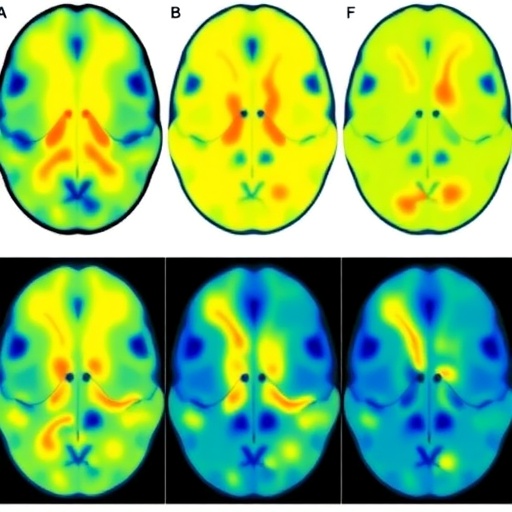

The investigators applied diffusional kurtosis imaging specifically to the white matter of neonates diagnosed with encephalopathy. This is crucial since white matter tracts are particularly susceptible to hypoxic-ischemic injury due to their high metabolic demand and developmental status during the neonatal period. DKI provides metrics such as mean kurtosis, axial kurtosis, and radial kurtosis, which correlate with tissue complexity and integrity beyond standard diffusion tensor imaging parameters. These more intricate measures allow a nuanced understanding of white matter alterations that accompany brain injury and repair processes.

By leveraging a cohort of neonates subjected to DKI scans shortly after injury and at follow-up stages, the study meticulously tracked changes in white matter microstructure that reflect injury severity. The robust imaging analysis revealed distinct kurtosis patterns that differentiate more severely affected infants from those with relatively milder impairment. This differentiation is essential for early prognostication and informed clinical decision-making, potentially guiding interventions in a timely manner to mitigate long-term disabilities.

The longitudinal aspect of this research is particularly striking. The authors demonstrated that DKI metrics evolve during the recovery phase, indicating that white matter displays dynamic reorganization and healing capabilities post-injury. Tracking these changes with high-resolution kurtosis imaging provides unprecedented insight into the brain’s resilience and plasticity in neonatal encephalopathy. Moreover, correlating imaging biomarkers with neurodevelopmental outcomes helped validate DKI’s predictive potential in real-world clinical contexts.